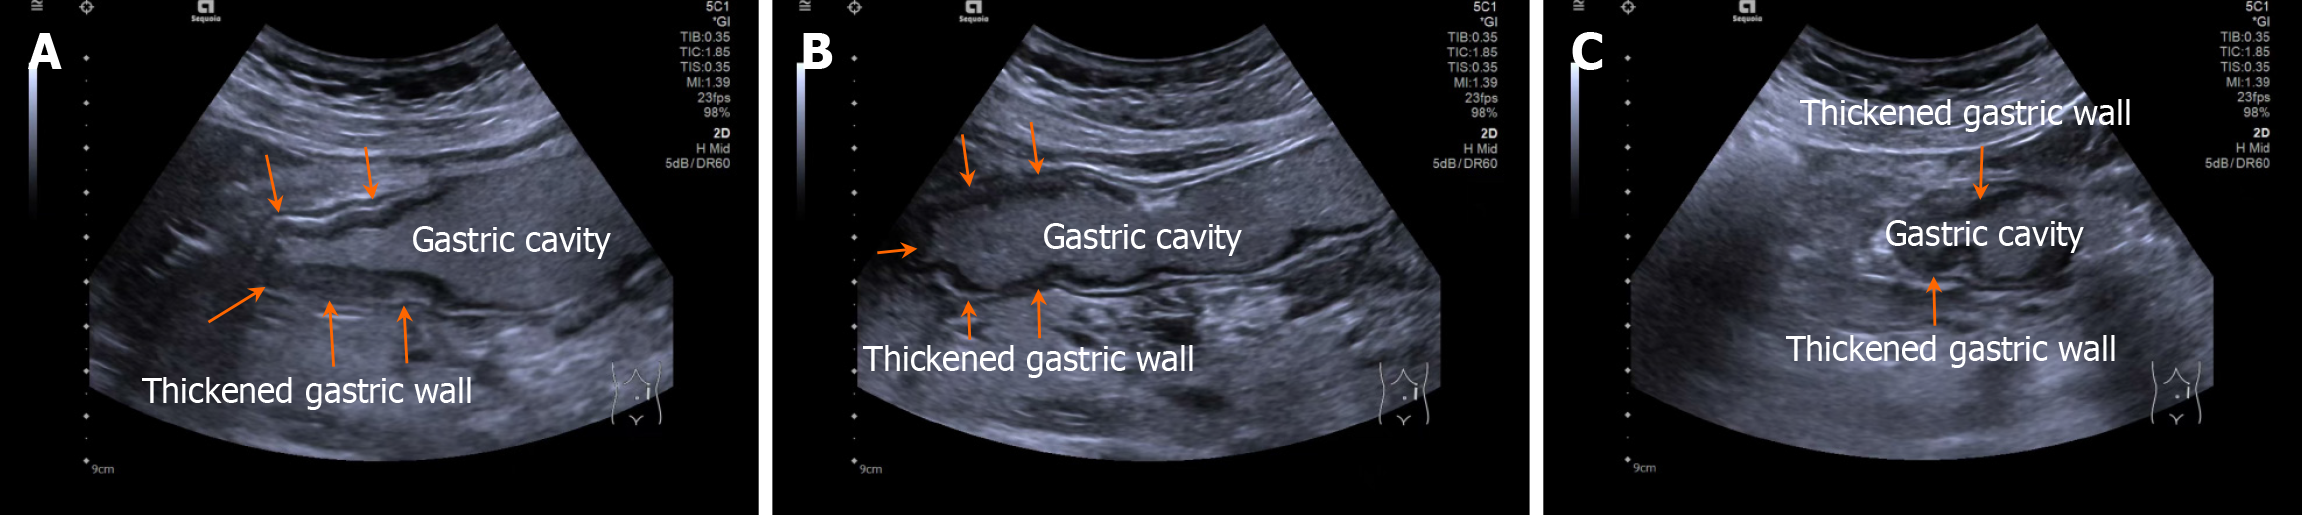

Patients fasted for > 8 hours and orally ingested 500 mL of prepared gastrointestinal contrast ultrasonography agent (Huzhou Dongya Medical Supplies Co., Ltd., Zhejiang; medical device registration number 20212060179) 5 minutes before the examination using a Siemens-SEQ1 color ultrasonography diagnostic device (registration number: National medical device registration import 20192060012) for gastrointestinal contrast ultrasonography. During the examination, the patient was adjusted to different positions, including supine, left and right lateral decubitus, and semi-sitting, with an appropriate amount of ultrasonography coupling agent applied. A probe was used to perform multi-plane scanning of the digestive tract from the cervical esophagus to the duodenum, with frequency and mechanical index set at 2-4 MHz and 0.07, respectively. After the basic contour structure of the stomach was clearly displayed, the thickness of the gastric wall, peristalsis, and the distribution of contrast agent in the gastric cavity were observed in detail. Representative images are shown in Figures 1 and 2.